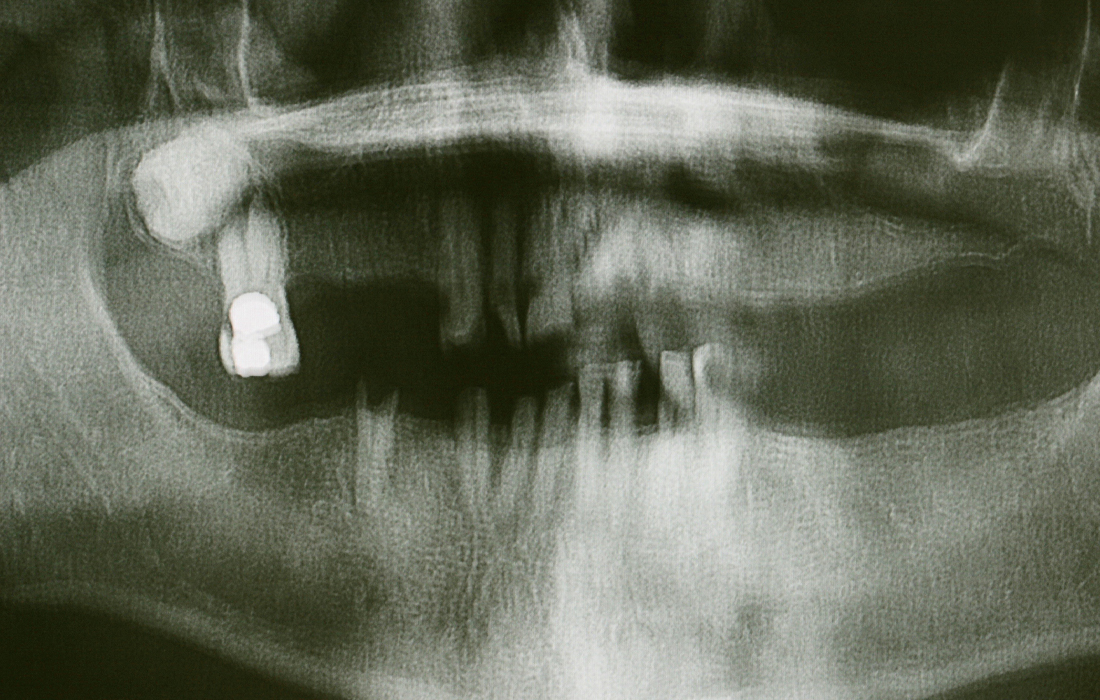

Replace Select and Hahn Tapered Implant x-ray

The patient, whom Dr. Hahn has been treating for several decades, has received implant restorations on many occasions to replace teeth lost due to fracture or decay. Placing implants is one of the best means of patient retention, as many people value the ability to receive the full circle of care from their general dentist. Note the various implant systems, all of which Dr. Hahn designed based on his clinical experience and observations over the last 50 years.